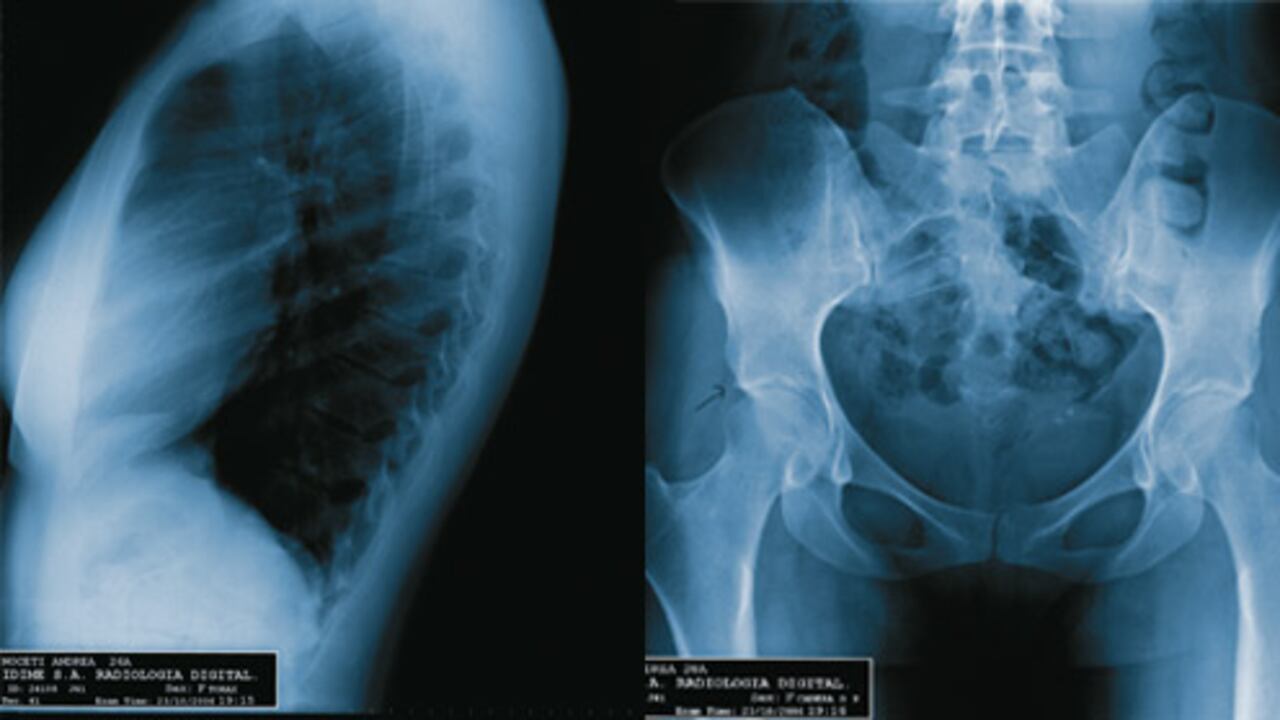

No se percibe ninguna prótesis. En la pelvis se ve una pequeña calcificación en la vejiga que no reviste mayor gravedad. Las relaciones articulares tienen simetría y características normales. Toda la región pulmonar está libre de nódulos. Los tejidos blandos y la estructura ósea no evidencia alteraciones. Su corazón es de tamaño normal y muestra una posición adecuada.